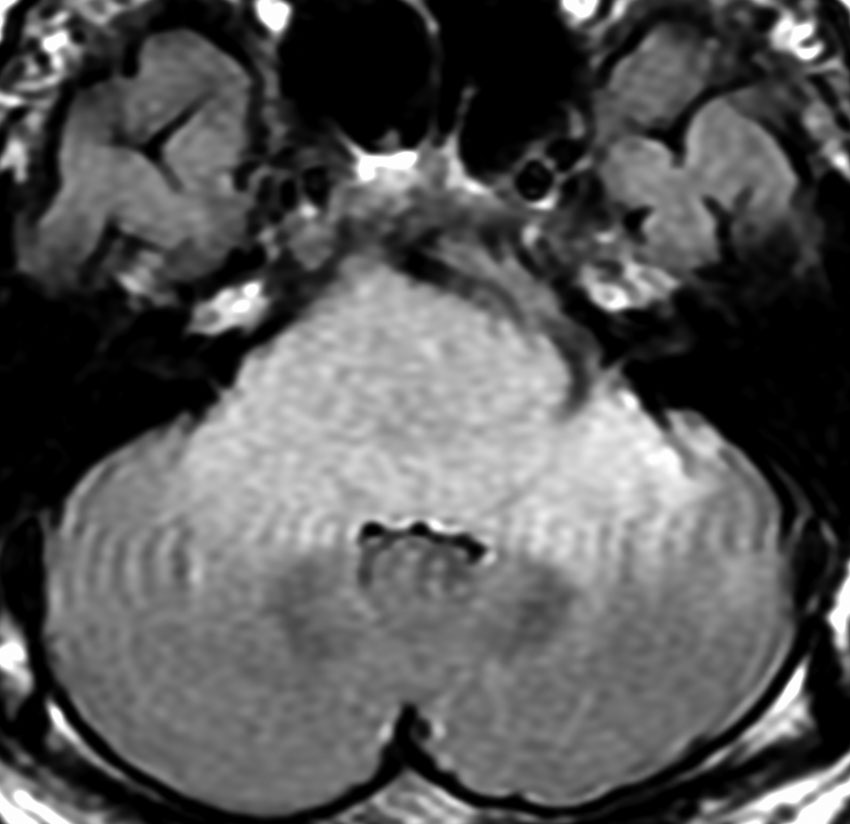

MRI画像所見 60代で嚥下障害と構音障害で発症した例

延髄から中脳まで腫瘍があって脳幹部が腫れています。この画像ですと,小児のびまん性橋膠腫(DIPG,びまん性正中グリオーマ)のように見えます